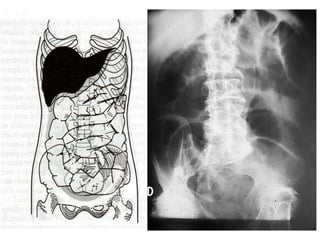

RADIOGRAFÍA SIMPLE

• Bipedestación:

– Imágenes gaseosas por encima del obstáculo al

principio

– Imágenes hidroaéreas tras 3-6-horas de evolución

• Decúbito supino:

– Yeyuno: Parte alta y media izquierda del abdomen

– Íleon: Parte baja y media derecha del abdomen

Ambos tienen una distribución en la zona central de las

asas.

–Intestino delgado

• Imagen en tubos de órgano

• Imagen en cuentas de rosario

• Imagen en tablero de damas

• Imagen en pila de monedas

• Imagen en peldaños de escalera

−Intestino grueso: Distribución periférica

• Menor número de burbujas, mayor tamaño y

localización periférica

• Imagen en balón o en arco

• Se observan la haustras

• Ausencia de gas en ampolla rectal en

obstrucciones distales